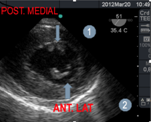

Los músculos papilares son 2, el anterolateral, que recibe doble irrigación (de las arterias circunfleja y descendente anterior, mientras el músculo póstero medial es irrigado por una sola arteria (la coronaria derecha o la circunfleja).

Figura 4: imagen a 51° transgástrica mediopapilar, músculos papilares anterolateral(1) y posteromedia(2).